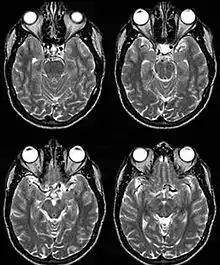

Fig. 1: Dolichoectasia of the suprasellar segment of the left internal carotid artery with compression of the optic chiasm

Internal carotid artery dolichoectasia is particularly interesting because the artery normally already contains one hairpin turn. Seen in an MRI as two individual arteries at this hairpin, a carotid artery dolichoectasia can progress so far as to produce a second hairpin turn and appear as three individual arteries on an MRI. In the case of a dolichoectasia of the Internal Carotid Artery (ICD), the pathogenesis is primarily related to compression of the optic nerves at the optic chiasma (see Fig. 1 and 2).